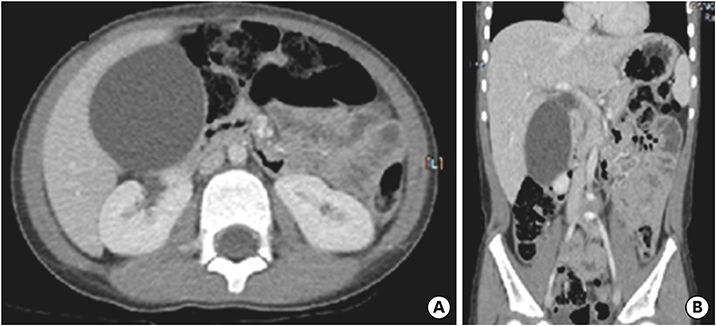

On the first day after admission, he received 2 g/kg IVIG and 50 mg/kg/day aspirin, following which his fever subsided and no further IVIG treatment was needed. His first echocardiography showed myocarditis (ejection fraction [EF], 45%) and mild ectasia of left main coronary artery (3.2–3.4 mm in diameter). On the second day after his admission, echocardiography (second follow-up) showed improved mild myocarditis (EF, 55%), improved ectasia of left main coronary artery (2.7–2.8 mm in diameter), and severe GB distension (8.9×4.6 cm in size), which possibly indicated GB hydrops (Fig. 2A). On the fourth day after his admission, although he had no fever and exhibited improvements in KD symptoms (i.e., eye injection, rash on abdomen, and cervical lymphadenopathy), he still complained of abdominal pain, distension, and tenderness of the RUQ. Follow-up laboratory findings were improved: neutrophilic leukocytosis (6,130 cells/mm3, with 33% neutrophils); decreased CRP (4.4 mg/dL), BNP (347 pg/mL), AST (40 U/L), and ALT (72 U/L); and improved hyperbilirubinemia (total bilirubin, 0.7 mg/dL). Echocardiography (third follow-up) showed normal completely improved carditis and still severe GB distension (10.2×5.5 cm in size) (Fig. 2B). Abdominal ultrasonography (US) was performed, which showed a markedly distended GB without stone, sludge, or wall thickening as well as normal bile ducts and liver morphology, which confirmed GB hydrops (Fig. 3A). On the sixth day after his admission, although his signs of KD had nearly disappeared, he still complained of abdominal discomfort, which had been moderately improving. The second follow-up abdominal US revealed a no notable change in GB distension compared to previous sonographic findings (Fig. 3B). An abdominal computed tomography (CT) scan was also obtained to exclude other hepatobiliary abnormalities, which showed similar findings as sonography, including a marked dilatation of the GB (8.0×5.5 cm in size) without stone, sludge, or wall thickening as well as normal bile ducts and liver morphology (Fig. 4). No complications necessitating surgical intervention had occurred and he was discharged 7 days after admission with only mild tenderness on the right upper-mid quadrant.

Fig. 2

Echocardiography showed severe gallbladder distension (A) 8.9×4.6 cm in size and (B) 10.2×5.5 cm in size.

Fig. 4

Abdominal computed tomography (A, B) performed at 10 days after fever onset showed marked distended gallbladder (8.0×5.5 cm in size) without wall thickening or sludge, which is consistent with gallbladder hydrops.